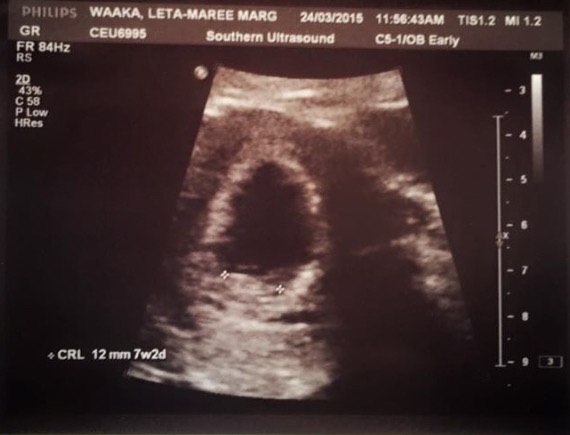

Had our first ultrasound yesterday! Found out I'm 11w2d which means I'm teetering between November/December. My due date as it stands is November 24th so right around thanksgiving It was just so surreal seeing the baby there with my DH. We were both just so happy to see a little baby there... it waved its arms a bit which was just so adorable.

Didn't catch what the heartrate was, but we definitely saw its little heart flickering Just so freaking amazing